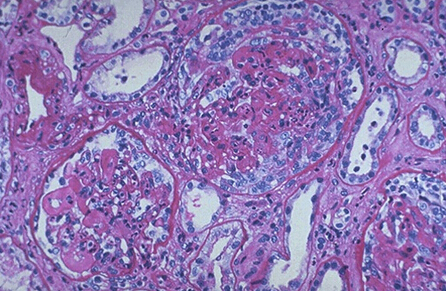

该研究中的四个临床中心入选了40例严重的SLE患者。在第1天和第7天,采用同种异体的脐带间充质干细胞静脉注射进行治疗。患者总的生存率为92.5%(37/40),脐带间充质干细胞移植后患者的耐受性良好,且未观察到与移植相关的不良事件。在随访3个月时,患者肾脏、造血和皮肤系统的BILAG分值(红斑狼疮评定指数)显着改善。对于那些有系统性红斑狼疮肾炎的患者,24小时蛋白尿在移植之后下降,与随访9月与12月时具有统计学差异。在第6个月时,血清肌酐和尿素氮下降到最低水平,由于有7例复发的病人,这些数值在9月和12月时略微上升。此外,移植之后血清白蛋白和补体3有所增加,在随访的第6个月达到顶峰,然后在第9和12月随访时,略有下降。